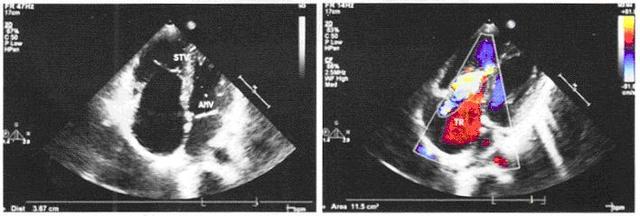

肝内外胆管梗阻 胆管上皮细胞恶性肿瘤可能

新生儿黄疸 多属于间接胆红素升高 即溶血性黄疸